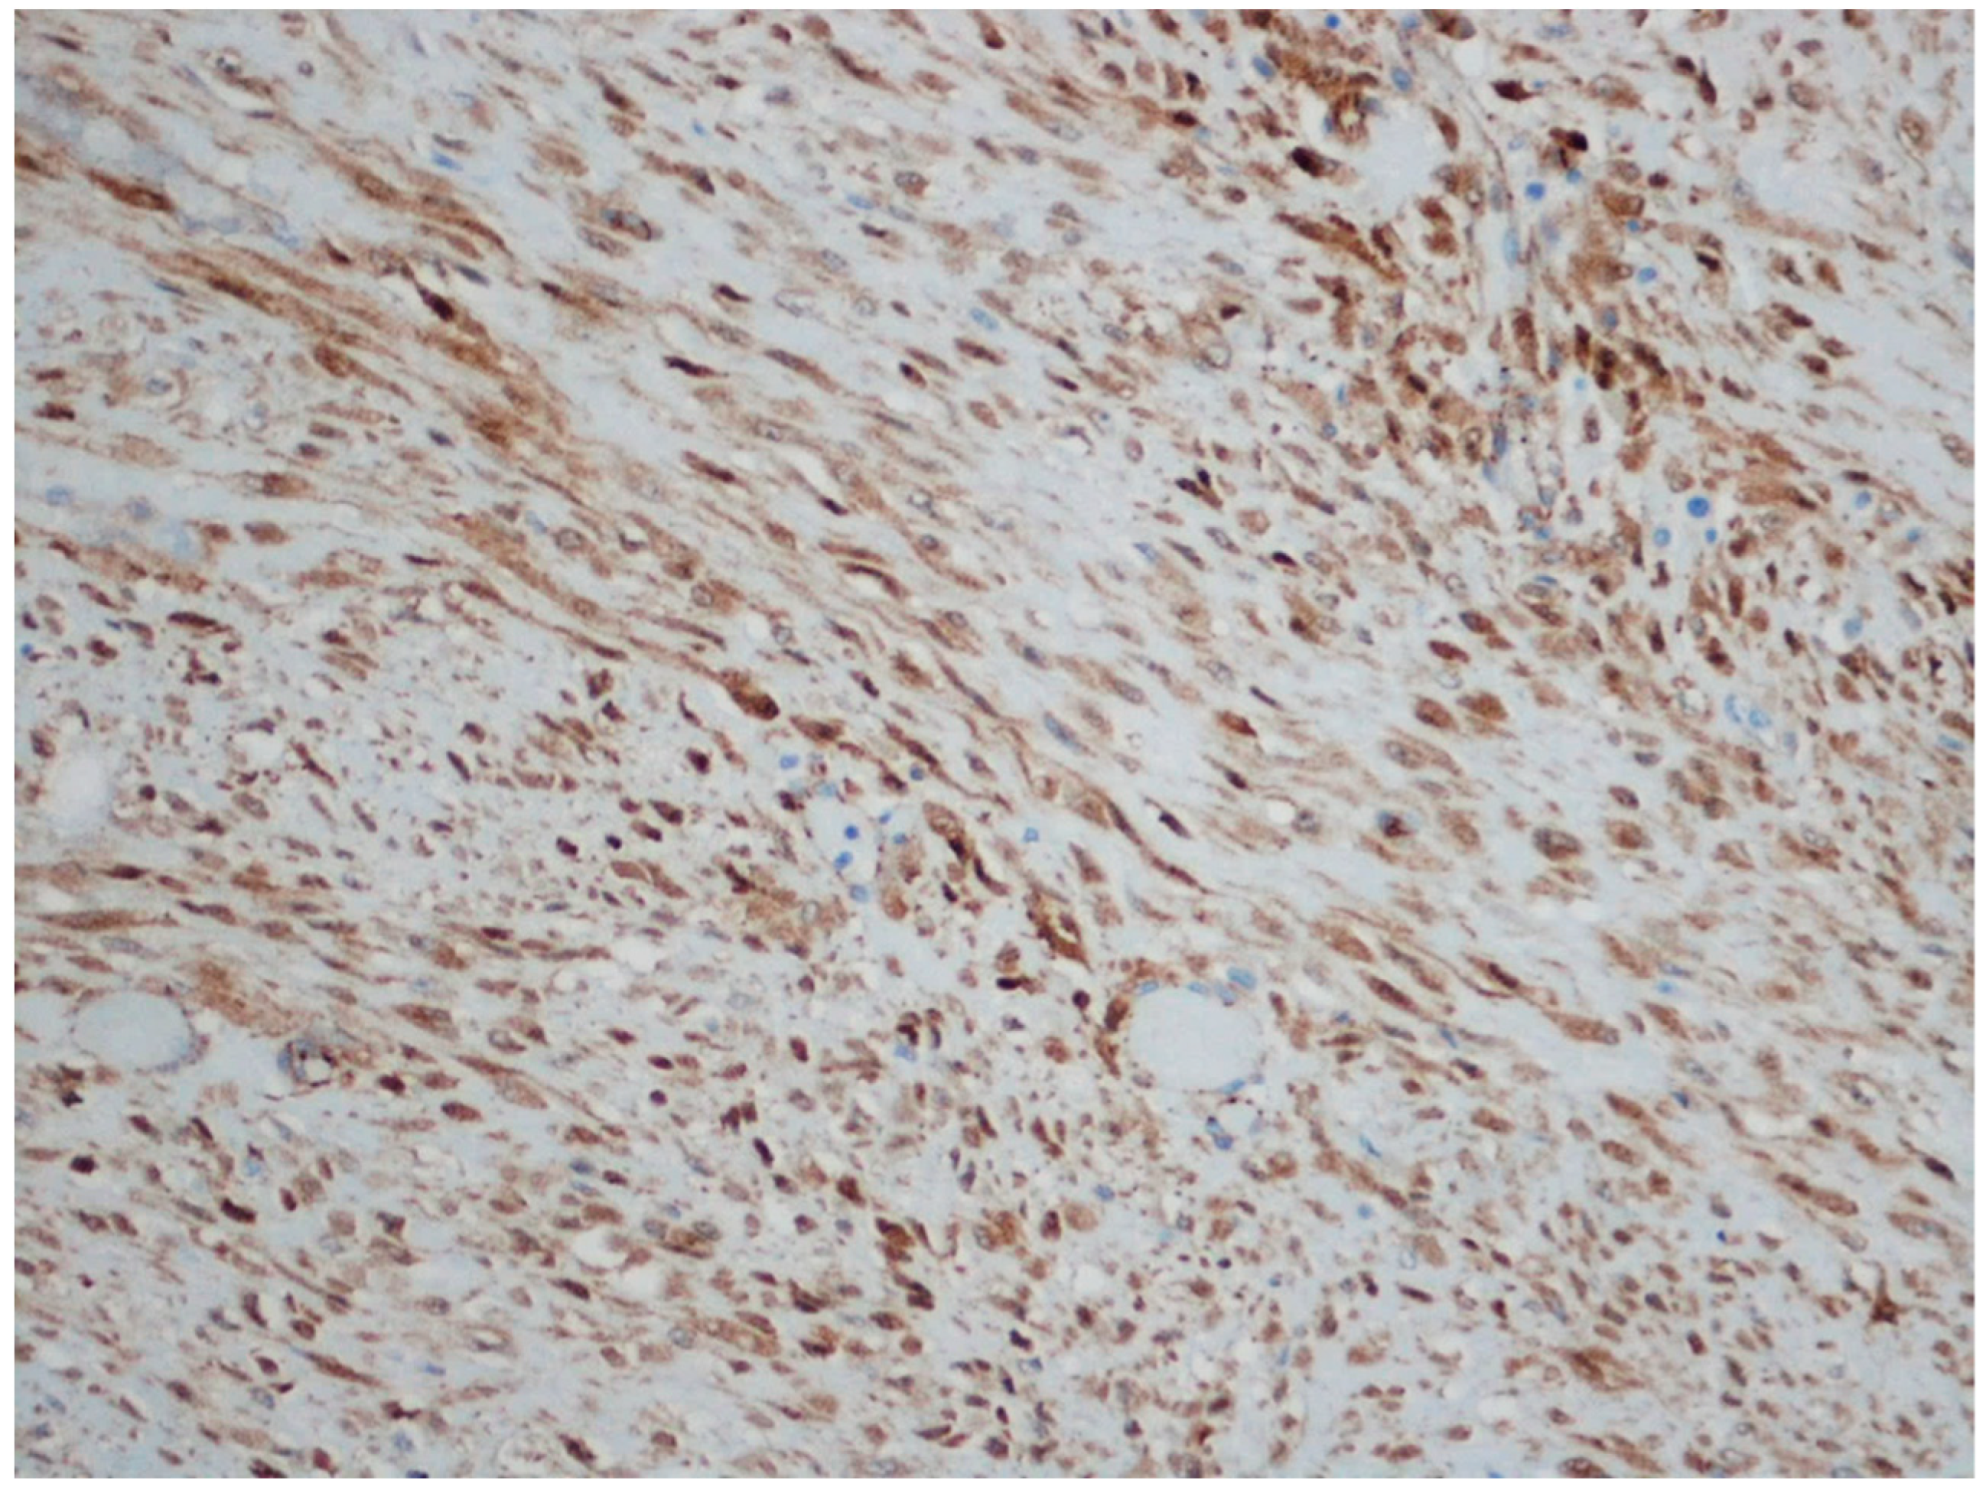

| Leiomyosarcoma | Very rare in the GI tract | Small intestine | Abdominal pain, obstruction | Of fascicles of spindle cells with atypia, centrally placed cigar-shaped nuclei, and eosinophilic fibrillary cytoplasm with high mitotic counts | α-sma, desmin, caldesmon |